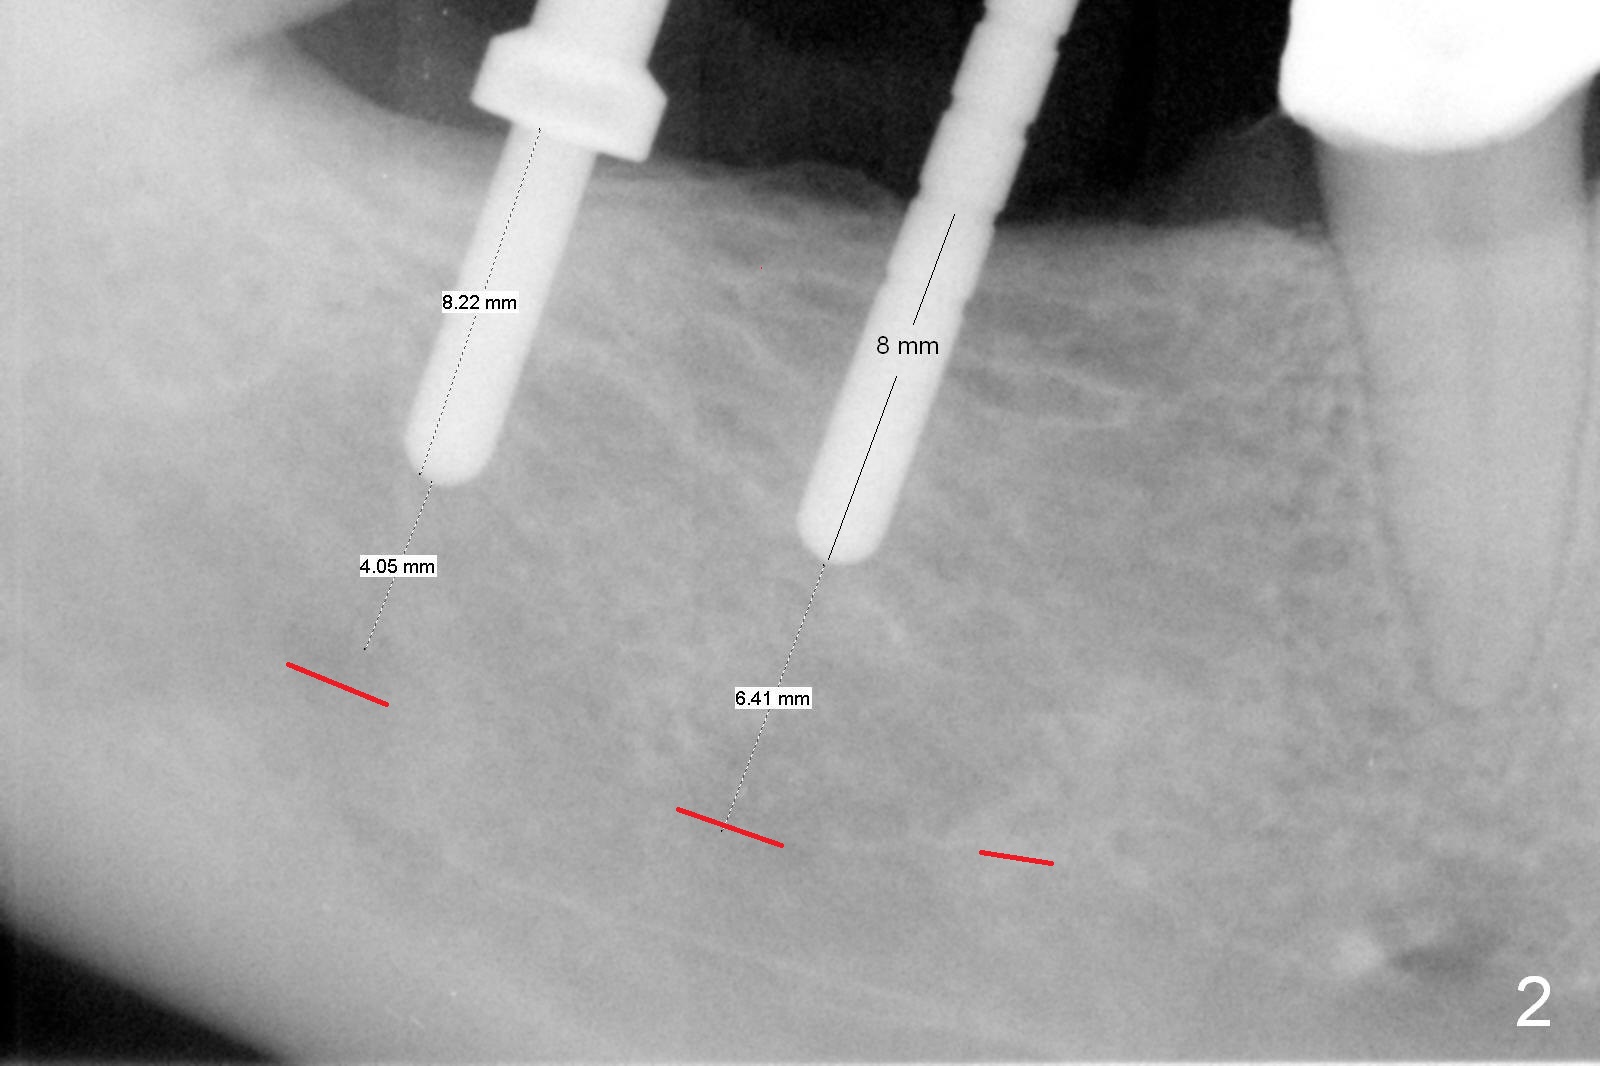

A preop photo shows different shape of pontics at #30 and 31 (Fig.1 <), suggesting different width of the edentulous ridge. Two of 8 mm parallel pins are inserted for position and trajectory (Fig.2 (red dashed line: the superior border of the Inferior Alveolar Canal). When they are removed from the osteotomy sites, the narrow ridge at #30 is shown (Fig.3). A 3x12 mm 1-piece implant is placed at #30, while a 4.5x10 mm 2-piece one at #31 (Fig.4,5). It appears that it is necessary to place an implant at #32, since the tooth #1 is present (Fig.5). The suggestion is rejected by the patient due to finance. After extraction of the tooth #32 and insertion of collagen plug, an immediate splinted provisional is fabricated to cover the #32 socket as well (Fig.6). The provisional is modified (to remove the portion that covers #32 socket) 3-4 weeks postop.